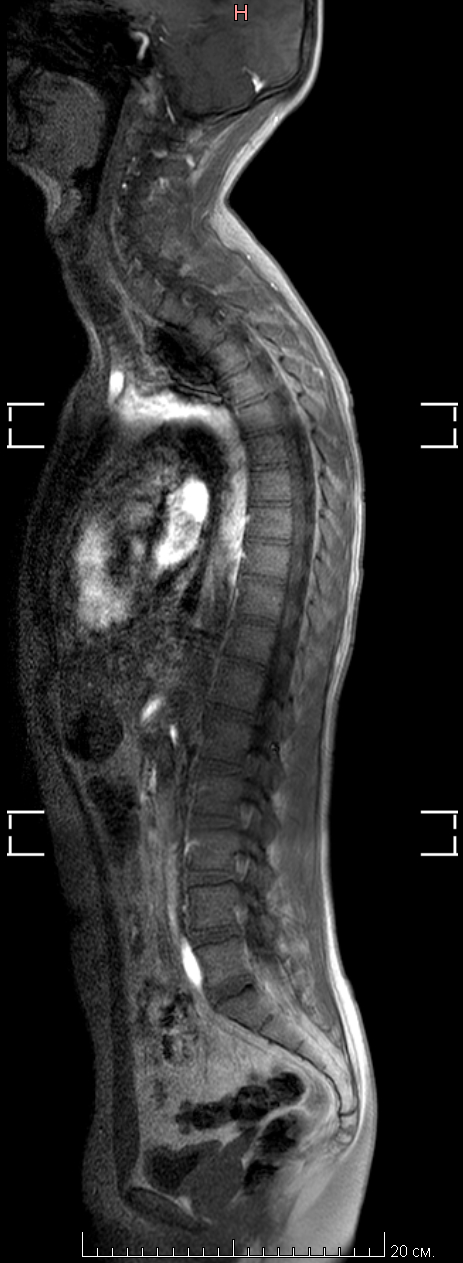

МРТ всех отделов позвонка

К этому посту Мое первое МРТ в 32 годика и этому Пикабу, нужна помощь по здоровью(Невролога(Но это не точно))

Пришло заключение от МРТ центра, я понимаю что надо идти еще на консультацию невролога и т.д. Но может кто из пикабушников сможет расшифровать по нашему, что и как.

Ну и что мне дальше делать.

Делал я МРТ всех отделов позвоночника. Лежал в аппарате полтора часа.

По самому МРТ, может кто тут разбирается, я приложу пару снимков, так как заключение будет только в понедельник. Может кто и поможет. Но, как сказала врач в центре МРТ, с моей симптоматикой, надо делать МРТ головного мозга =(